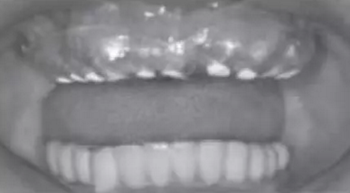

患者,男,66歲,上頜牙松動多年。口腔檢查:下頜為種植體固定修復,修復體與種植體邊緣密合,扣(-),松(-)。15、16、17、26、27缺失。13、12、11、21固定橋修復,其中13、21為固位體,12、11為橋體。13、21修復體邊緣不密合,扣(+),松Ⅲ°,牙齦退縮至根上1/3,牙齦紅腫,探有約7mm深牙周袋(圖1)。14、22、24、25扣(+),松Ⅲ°,探牙周袋約有5mm。23扣(+),松Ⅱ°。

圖1 術前口外頜面照及口內(nèi)照